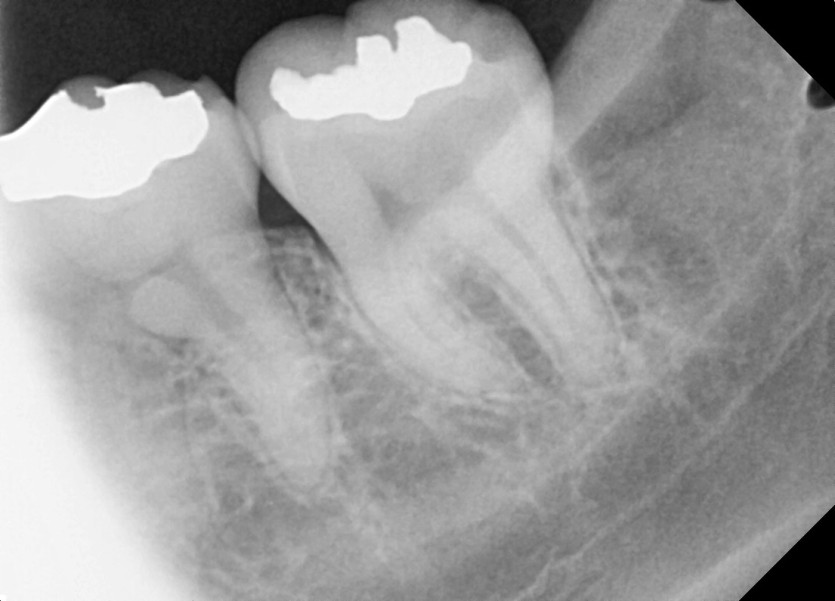

#18,28,38,48 사랑니 발치

구강 외과 전문의가 당일 발치했습니다.